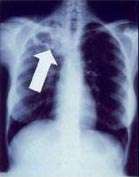

Radiology (X-rays) is used in the diagnosis of tuberculosis. Abnormalities on chest radiographs may be suggestive of, but are never diagnostic of, TB but can be used to rule out pulmonary TB.

In active pulmonary TB, infiltrates or consolidations and/or cavities are often seen in the upper lungs with or without mediastinal or hilar lymphadenopathy.[1] However, lesions may appear anywhere in the lungs. In HIV and other immunosuppressed persons, any abnormality may indicate TB or the chest X-ray may even appear entirely normal.[1]

Old healed tuberculosis usually presents as pulmonary nodules in the hilar area or upper lobes, with or without fibrotic scars and volume loss.[1] Bronchiectasis and pleural scarring may be present.

Abnormalities on chest radiographs may be suggestive of, but are never diagnostic of, TB.[1] However, chest radiographs may be used to rule out the possibility of pulmonary TB in a person who has a positive reaction to the tuberculin skin test and no symptoms of disease.